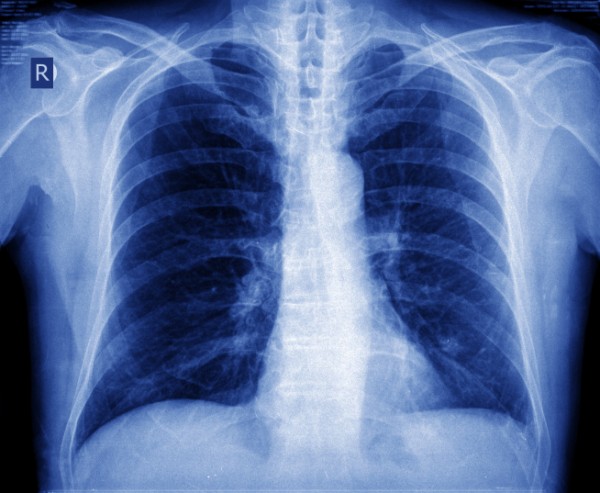

Pescara: simposio sul nodulo  polmonare. Esperti a confronto per parlare del tema “Il nodulo polmonare solitario: un tema antico che torna di attualità”.  Gli specialisti spiegano che i noduli polmonari sono molto diffusi nei fumatori incalliti e di solito si presentano sotto forma di  cicatrice, granuloma, oppure un’infezione, meno spesso un tumore.  Se vi siete sottoposti ad un esame al torace ed avete scoperto di avere un nodulo al polmone  è meglio rivolgersi allo  specialista. Comunque i dati dicono che in Italia su 5 mila soggetti esaminati, con più di 50 anni e forti fumatori, vengono trovati noduli nella metà dei casi, ma alla fine solo 50 risultano tumorali. Nella maggior parte dei casi sono benigni, dovuti, per esempio, a esiti cicatriziali di precedenti infiammazioni, come broncopolmoniti, a granulomi, oppure sono segno di infezioni come la tubercolosi. Altre volte, sono, invece, di natura maligna e quindi sono una spia di un tumore al polmone o di  metastasi polmonari di tumori di altra provenienza. La Tac , più che la radiografia , consente di rilevare noduli di dimensioni inferiori al centimetro nonché diversi parametri, tra cui densità, forma, presenza di calcificazioni e anche ricostruire l’aspetto volumetrico del nodulo, permettendo di valutarne con precisione la crescita nel tempo. L’analisi di tutti questi parametri orienta la diagnosi, evitando, in molti casi, inutili esami e tanta ansia. La prevenzione è anche in questi casi fondamentale e la prima regola è quella di non fumare e se si è stati  fumatori a lungo si può considerare l’opportunità di controlli periodici con la Tac dopo i 50 anni. Questo esame permette una diagnosi precoce di tumore al polmone nel 75% dei casi e cià  aumenta le possibilità di guarigione.